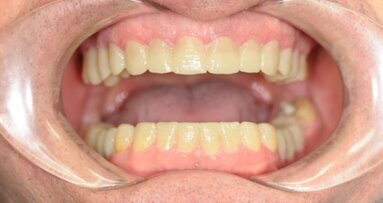

Pacjentka narzekała głównie na kolor oraz przerwy między zębami w odcinku przednim górnego łuku (Ryc. 2-6). Po zebraniu wywiadu medycznego oraz stomatologicznego wykonano badanie kliniczne i radiologiczne w celu ustalenia rodzaju problemu (związek z próchnicą, problem natury periodontologicznej lub endodontycznej).

Badanie kliniczne wykazało niski poziom higieny jamy ustnej, przerost dziąseł, widoczne przebarwienia wokół zamków z powodu palenia tytoniu, próchnicę w prawym górnym kle oraz koronę na metalu na zębie 22 (Ryc. 2-6). Po zdjęciu zamków wykryto niewielka demineralizację szkliwa wokół nich. Zauważono też przesunięcie linii pośrodkowej łuku górnego w stosunku do linii pośrodkowej twarzy (Ryc. 1). Badania kliniczne i radiologiczne nie wykazały nieprawidłowości w odcinkach bocznych.

Zabieg periodontologiczny przeprowadzony został w Klinice Periodontologii. Przed wybielaniem upewniono się, że powierzchnia szkliwa wolna jest od płytki nazębnej, kamienia oraz przebarwień (Ryc. 10). Aby zapobiec interakcji protein i enzymów ze śliny ze środkiem wybielającym, delikatnie oczyszczono zęby pastą profilaktyczną.